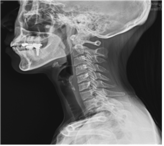

일자목증후군, 평상시 올바른 자세 유지해야

- 2018-02-25 21:12

- 김경애 기자